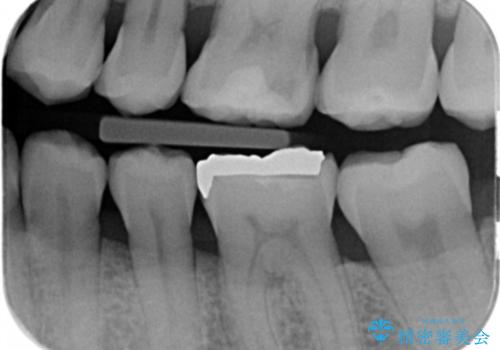

- 銀の詰め物が目立つので白くしたいとのことで来院。

拡大鏡下で銀の詰め物を除去して虫歯がない事を確認して

白い詰め物(e-maxインレー)にてやりかえを行いました。

- e-maxインレー 7.7万円 費用は治療当時の料金となります